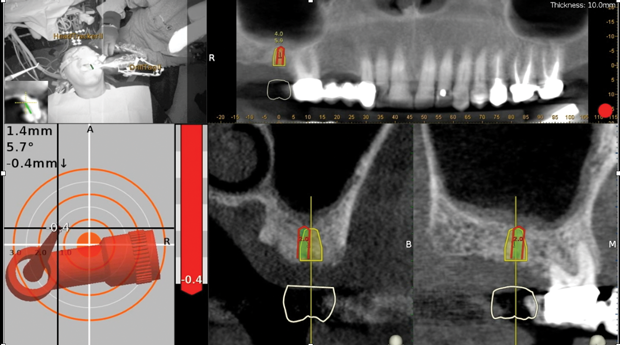

Fig 6. Realtime

tracking of osseodensification bur upfracturing sinus floor but

not exceeding 3 mm. Red depth control indicator and bull’s eye target

deliver real-time feedback to position.

Figure 6

Fig 11. Trace and place (TAP) technique utilizing existing implants

as radiographic markers.

Figure 11